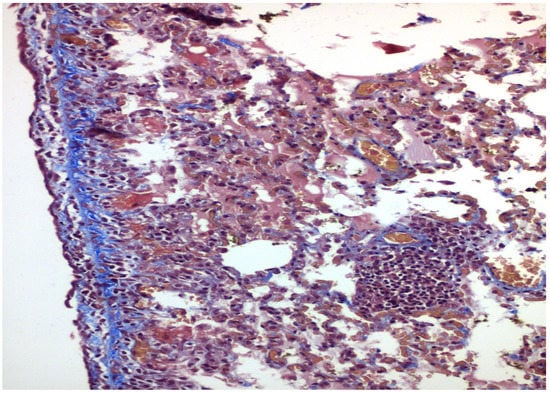

- With talc, there was a statistically significant difference in the inflammation provoked in 6 days compared to 3 days regarding parietal pleura (p = 0.002) (Figure 11); regarding visceral pleura, this could not be measured, as inflammation was high in both groups (grade II–III).